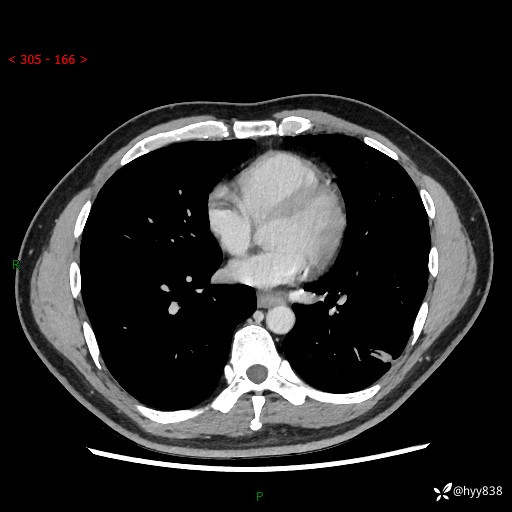

现病史:患者3月前出现胸闷,卧位时加重,坐位时缓解,无咽痛、咳嗽,无头痛,无全身酸痛,无结膜充血,无胸痛、心慌,无咯血,无呼吸困难,无咳痰,2024-07-02于当地市第一民医院行胸部CT,结果不详,2024-07-05就诊于我院急诊内科,行胸部CT同时增强,结果示:左肺下叶多发结节灶,考虑感染可能。今患者为求进一步诊治来我院,门诊以“肺部感染”收入我科。 患者本次起病来精神、食欲、睡眠尚可,大小便可,体力,体重无明显变化。

胸部CT平扫+增强

各期CT值:30hu 90hu 77hu